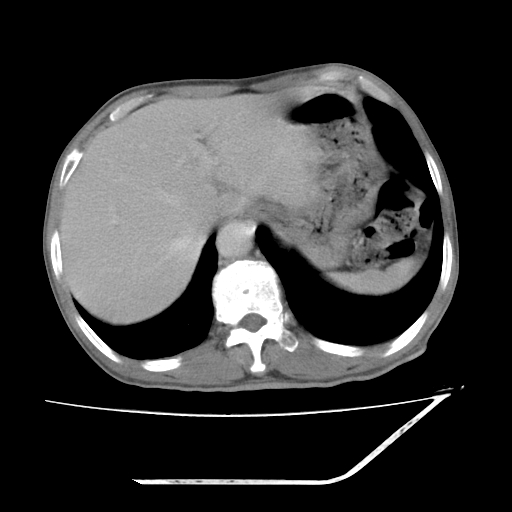

平扫

考虑右肾盂癌,肾动脉受侵,右肾功能减退,右肾盂输尿管积水,管壁增厚,考虑种植转移,应该把下面扫完的

支持右侧肾盂癌伴肾静脉瘤栓形成可能性大,右肾结石.肝右叶后段低密度影,不除外转移.

右肾盂旁ca并肾静脉瘤栓形成/肾功能降低。

右肾结石。

支持 右侧肾盂癌伴肾静脉瘤栓形成可能性大,右肾结石;肝右叶后段低密度影,不除外转移。

1.右侧肾盂癌伴肾盂积水。

2.肾脏功能减退,原因有:(1)肾动脉受侵。(2)肾静脉受侵(3)肾积水,等。本例,肾动脉显影较好,但受压明显;肾静脉无明显显示,受压或静脉癌栓,下腔静脉腔内未见明显充盈缺损。

3.右侧上段输尿管扩张,原因:(1)积水所致;(2)种植。